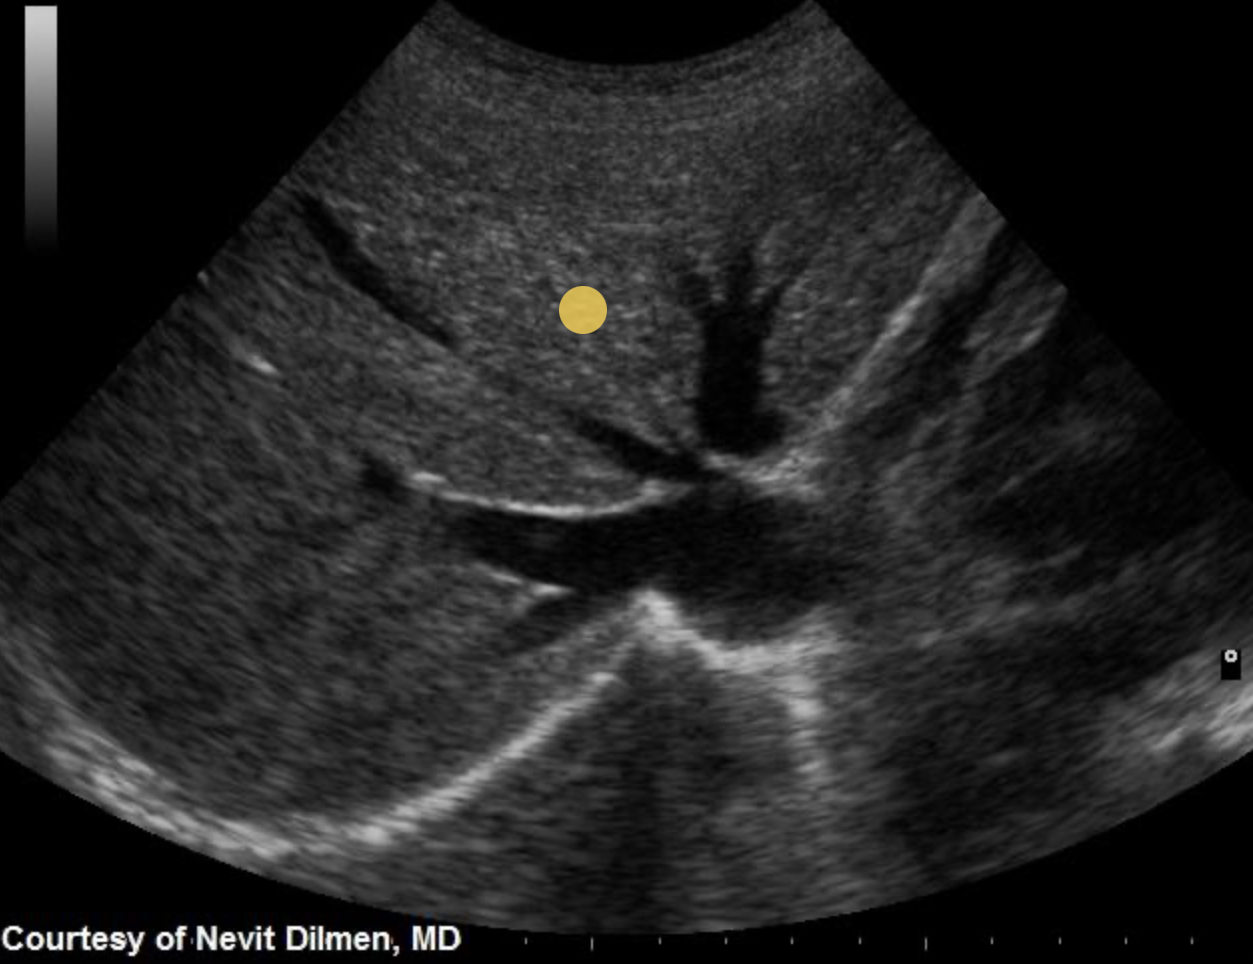

What structure is indicated by the purple circle?

Portal triad